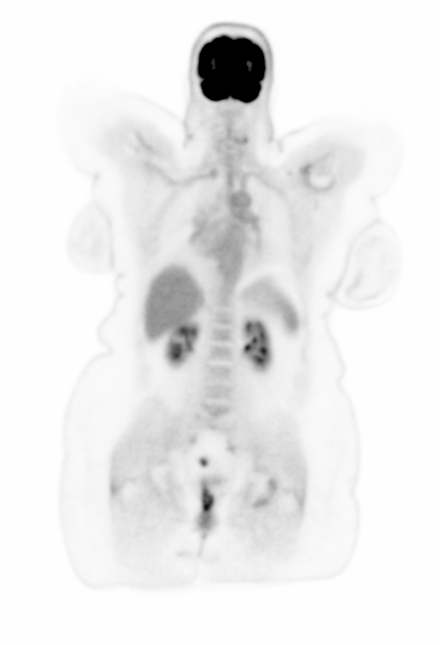

Figure 7 shows three clinical \acFDG dataset examples. The \acDLSE-corrected images are visually very similar to the \acSSS-corrected images. Note that the second \acPET acquisition was performed in arms-down position while our model was trained in arms-up position. However this does not seem to affect the results.

Examining the profile lines in the first row, which displays a breast lesion in a female patient, reveals similar patterns to those observed in the simulated images in Figure 4, with lower activity in the region between the lungs using \acSSS compared to \acDLSE. However, the activities within the lesion are very similar for both \acDLSE and \acSSS.

In the second row dataset, \acDLSE provides better contrast on the nodules than \acSSS, showing similar activity levels between the nodules but with a higher activity peak.

The last dataset shows kidney structures in a large morphology patient (98 kg). The \acSSS-corrected image exhibits an overall higher activity than the \acDLSE-corrected image. After manual segmentation of the kidneys and automatic segmentation of its structures using the FLAB algorithm [37], the contrast is found to be slightly higher in the \acDLSE corrected \acPET images. The contrast is 2.3 with \acDLSE correction, compared to 2.2 with \acSSS correction and 1.8 in the uncorrected image.

| No correction | DLSE | SSS | Profiles |

![]() |

| Sex | Weight | Dose | Coincidences | |

| 1st row | Female | 52 kgs | 160 MBq | 3.0 billions |

| 2nd row | Male | 80 kgs | 244 MBq | 4.7 billions |

| 3rd row | Female | 98 kgs | 297 MBq | 3.8 billions |

Figure 8 shows the correlation between activities in \acDLSE- and \acSSS-corrected \acPET images across different organs. Considering all \acpROI, the relationship between the mean activities of both methods is given by the regression function . Activity values are similar in the brain and lung regions, but \acDLSE-corrected images tend to show higher activity levels in the liver compared to \acSSS-corrected images.